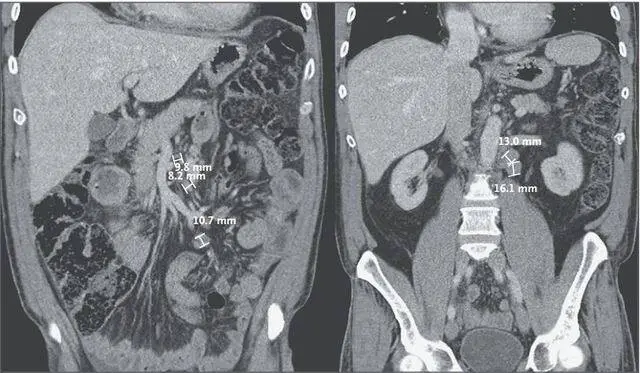

图 1. 腹部 CT。胸部和腹部 CT 扫描可见轻度的间质性肺水肿和少量双侧胸腔积液。主肺动脉增宽,直径为 30.9 mm,伴少量心包积液。腹部广泛的淋巴结肿大,可提示淋巴瘤,同时近端膨胀的空肠局部增厚。